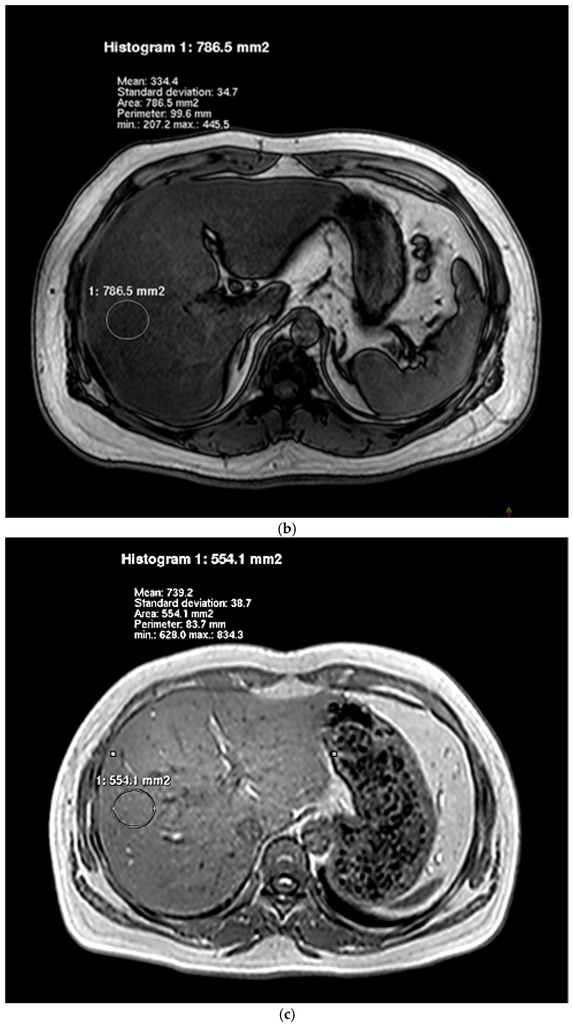

The degree of hepatic lipid contents assessed by IHL and HFF is presented in Table 2. For the examination by dual-echo MRI, the fat and water signals within a voxel were, respectively, additive and subtractive in the in-phase image and the opposed-phase image (Figure 1). In the images of NAFLD patients, there was a decrease of the signal intensity from the in-phase to an opposed-phase image. NAFLD patients showed significantly higher HFF than controls. Figure 2 showed typical examples of 1H spectra for a NAFLD patient (A) and a control subject (B). NAFLD group had higher IHL, which contrasted sharply with controls.

Figure 1.

Representative IP (a,c) and OP (b,d) images of livers obtained by using dual-echo sequence. Images of a NAFLD patient and a healthy individual were, respectively, Figure 1a–d.